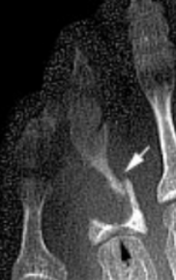

| What disease is this? What do the arrows indicate? | Gout Arrows = 'punched out' erosions |

| What disease is this? What indicates this? | Tophaceous gout. Soft tissue swelling surrounding the index finger PIPJ, with associated erosion and bone resorption |